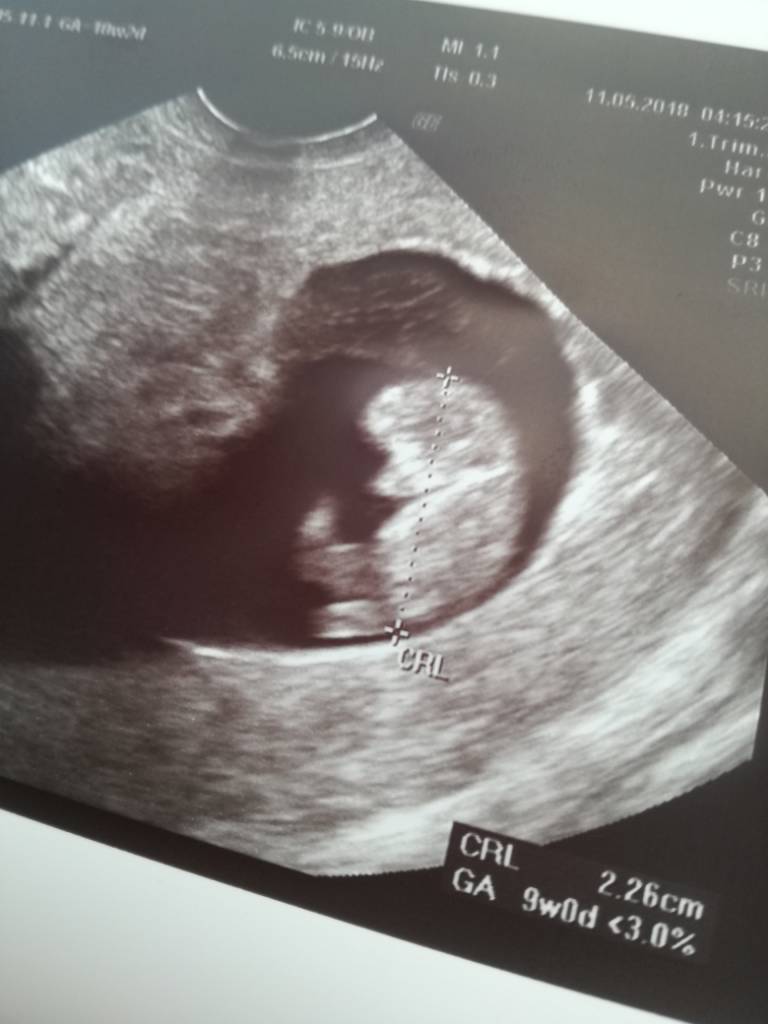

Cudnie to nasze dzidzie podobnie rosną moja tez prawie tyle [emoji7] może razem będziemy na porodówke jechac hihiJa po wizycie. Dzidzia rośnie ma 2,5 cm. Wszystko ok!. Bardzo się cieszę!